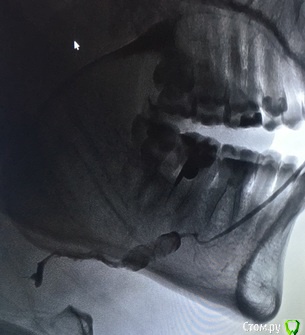

aleksei_sataev Опубликовано 14 декабря, 2017 Автор Поделиться Опубликовано 14 декабря, 2017 (изменено) Мало что видно на фото. Процесс заживления пошел ещё на предыдущем. Вам сейчас кроме как ждать полного заживления десны ничего особо не остаётся. Возможность проведения имплантации в этой зоне под большим вопросом,потребуется несколько пластических вмешательств. Добрый вечер уважаемые врачи.После удаления прошло 2,5 недели. 1.Может ли быть в теории, что всё таки пластика не понадобится? Т.е стенка сама собой затянется без пластики? https://cloud.mail.ru/public/HYZX/8hw9HD3yD 2.Есть у меня пару камней больших размеров, один в протоке в подчелюстном, а другой пока не понятно, есть ли в 2017 году щадящие операции? Например всунуть какой нибудь сиалоскоп и раздробить или оперативно убрать не трогая слюную железу? Повторюсь второй камень может быть в самой железе, рентгена пока нет...Просто бесспокоить уже начинает..В последний раз делал снимок этой области лет 10 назад... 3.В гайморовых пазухах у меня есть пару кист которые мне жизнь портят, почитал забугорную прессу и остановился на FESS, практикуется ли у нас в России данный метод? Спасибо большое.Извините за множество вопросов, просто решил основательно собой заняться. Изменено 14 декабря, 2017 пользователем aleksei_sataev Ссылка на комментарий

Irouil Опубликовано 15 декабря, 2017 Поделиться Опубликовано 15 декабря, 2017 Правильно решили. 1) с вероятностью 99 из 100 костная пластика потребуется. Мягкотканная 100 из 100. 2) я не слышал про дробление и сиалоскоп, честно сказать этим особо не занимаюсь, но из протока достать можно из полости рта достаточно аккуратно. Разрез небольшой и все. 3) конечно, fess в разных вариантах практикуется в РФ. Надо смотреть КТ чтобы говорить в какой степени и каким доступом требуется вмешательство. 2 Ссылка на комментарий

aleksei_sataev Опубликовано 18 января, 2018 Автор Поделиться Опубликовано 18 января, 2018 с вероятностью 99 из 100 костная пластика потребуется. Мягкотканная 100 из 100. Доктор, а Вы, как считаете? Чуть лучше стало? Ссылка на комментарий

Irouil Опубликовано 1 февраля, 2018 Поделиться Опубликовано 1 февраля, 2018 Доктор, а Вы, как считаете? Чуть лучше стало? Мои прогнозы не изменились и до того как Вы сделаете КТ не изменятся. Но трагедии нет, все решаемо. 1 Ссылка на комментарий